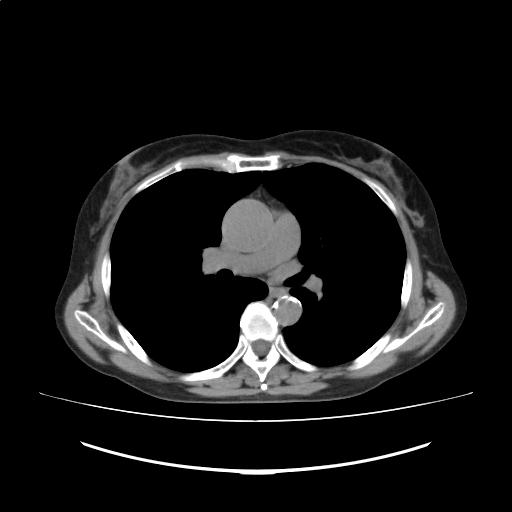

症例画像5

画像診断検査結果5

CTスライス画像

(Findings)

肺野に結節影を認めない。

縦隔リンパ節の有意な腫大および胸水を認めない。

上行大動脈は軽度拡大しており、最大径約43mmである。前回と比較して著変なし。

(Impression)

多発肺結節・縦隔リンパ節腫大:r/o 多発肺転移

肝嚢胞

左腎石灰化

軽度脾腫